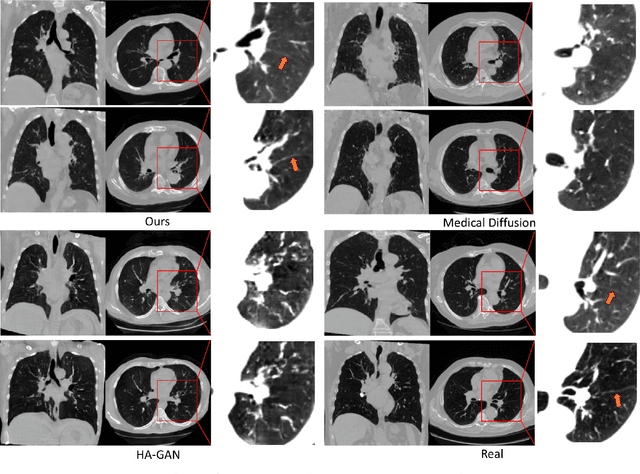

Abstract:This paper introduces an innovative methodology for producing high-quality 3D lung CT images guided by textual information. While diffusion-based generative models are increasingly used in medical imaging, current state-of-the-art approaches are limited to low-resolution outputs and underutilize radiology reports' abundant information. The radiology reports can enhance the generation process by providing additional guidance and offering fine-grained control over the synthesis of images. Nevertheless, expanding text-guided generation to high-resolution 3D images poses significant memory and anatomical detail-preserving challenges. Addressing the memory issue, we introduce a hierarchical scheme that uses a modified UNet architecture. We start by synthesizing low-resolution images conditioned on the text, serving as a foundation for subsequent generators for complete volumetric data. To ensure the anatomical plausibility of the generated samples, we provide further guidance by generating vascular, airway, and lobular segmentation masks in conjunction with the CT images. The model demonstrates the capability to use textual input and segmentation tasks to generate synthesized images. The results of comparative assessments indicate that our approach exhibits superior performance compared to the most advanced models based on GAN and diffusion techniques, especially in accurately retaining crucial anatomical features such as fissure lines, airways, and vascular structures. This innovation introduces novel possibilities. This study focuses on two main objectives: (1) the development of a method for creating images based on textual prompts and anatomical components, and (2) the capability to generate new images conditioning on anatomical elements. The advancements in image generation can be applied to enhance numerous downstream tasks.